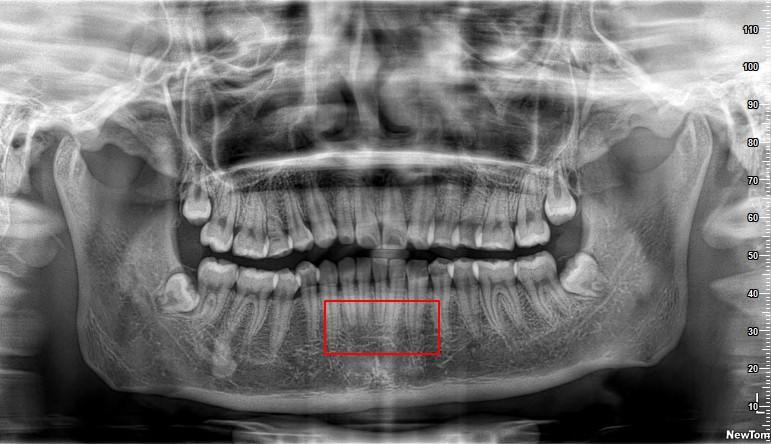

大龄想正畸但拔智齿时候看片子牙根偏短还能正畸么

图片尺寸4032x3024